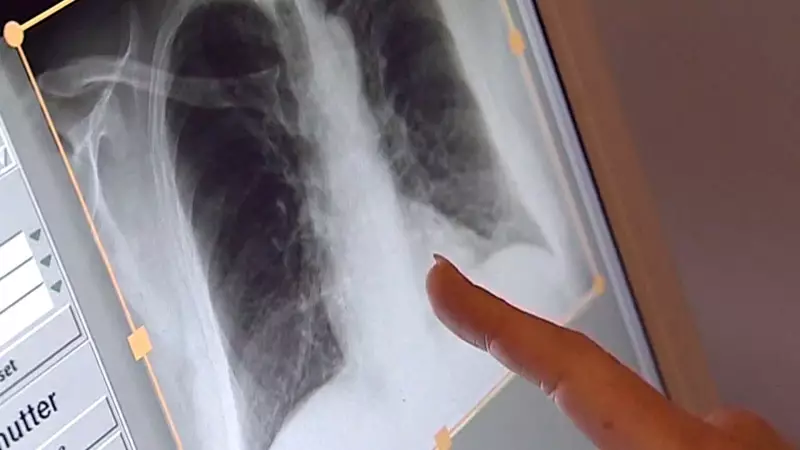

Data analyzed by health authorities confirms a steady increase in tuberculosis (TB) diagnoses in recent years. While the disease is often associated with historical periods, it remains a present and serious bacterial infection. Montreal, as Quebec's most populous urban centre, has reported a notable portion of these new cases. The rise is not confined to the metropolis, however, with other areas of the province also experiencing higher incidence rates.

Dr. Faiz Ahmad Khan, a respirologist and expert in tuberculosis, has been vocal about the situation. He explains that the increase is multifaceted, involving complex social and medical factors. "We are seeing a rise that demands our attention and a coordinated public health response," Dr. Khan stated. He emphasizes that while tuberculosis is treatable and curable with a proper course of antibiotics, the path to diagnosis and sustained treatment is fraught with barriers for many.